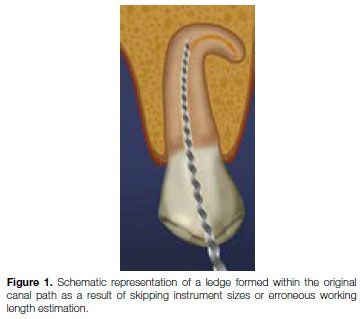

The patient, a 49 year old female presented with percussion sensitivity on her mandibular, right second molar. A peri-apical radiograph revealed that all the root canals were prepared short of working length, and showed evidence of peri-apical pathology around the mesial roots (Figure 2).